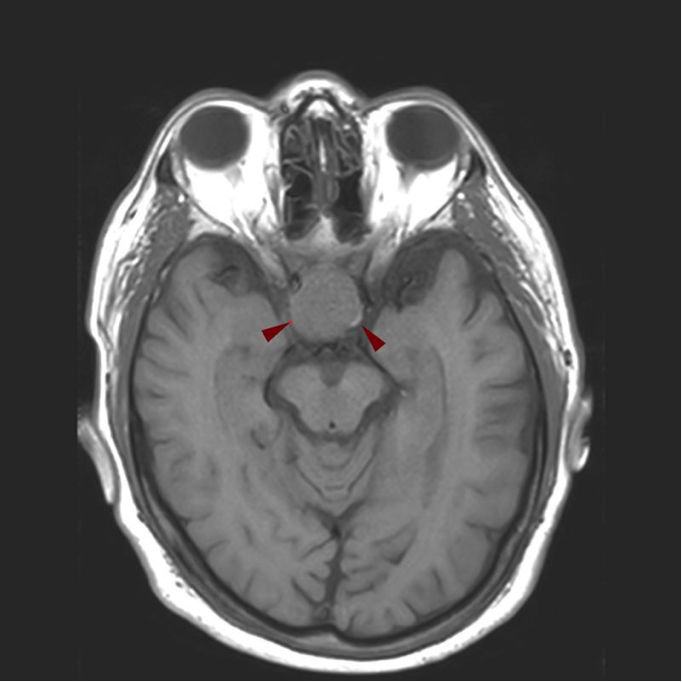

Η διάγνωση του αδενώματος της υπόφυσης βασίζεται σε μία ολοκληρωμένη ιατρική αξιολόγηση που περιλαμβάνει την κλινική εξέταση του ασθενή και εξειδικευμένο εργαστηριακό και απεικονιστικό έλεγχο.

Βασικές εξετάσεις είναι ο ορμονολογικός έλεγχος, με προσδιορισμό των επιπέδων των ορμονών στο αίμα και, σε ορισμένες περιπτώσεις, στα ούρα, καθώς και ο απεικονιστικός έλεγχος του εγκεφάλου, κυρίως με μαγνητική τομογραφία.

Σε περιπτώσεις μακροαδενωμάτων μπορεί να απαιτηθεί και αξονική τομογραφία. Ανάλογα με τον τύπο και το μέγεθος του αδενώματος, ενδέχεται να χρειαστεί οφθαλμολογικός έλεγχος ή πρόσθετες εξετάσεις, όπως έλεγχος οστεοπόρωσης σε ασθενείς με σύνδρομο Cushing.

Αδένωμα Υπόφυσης Διάγνωση